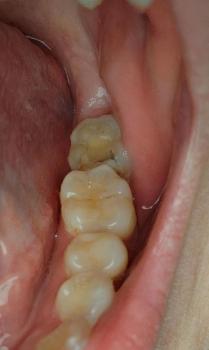

Professional Comment